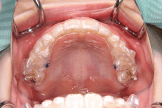

マウスピース型カスタムメイド矯正歯科装置(製品名インビザライン 完成物薬機法対象外)の場合

治療のゴールは、顎の大きさを広げるだけではなく、それと同時に気になっている歯のねじれやガタガタ、隙間などに対しても細かく歯の位置を修正することです。

- 治療期間は、18か月。

- 取り外しができます。食事や歯磨きも普段通りに行えます。矯正装置による虫歯のリスクは固定式の装置に比べ格段に少ないと考えられます。

- 定期的(平均2週間に1度)に新しいマウスピースに交換していくので衛生的です。

- 透明なマウスピースを装着するので、装置をつけていても目立ちません。

- シミュレーションソフトによる治療計画の立案と治療中の経過検証が可能です。